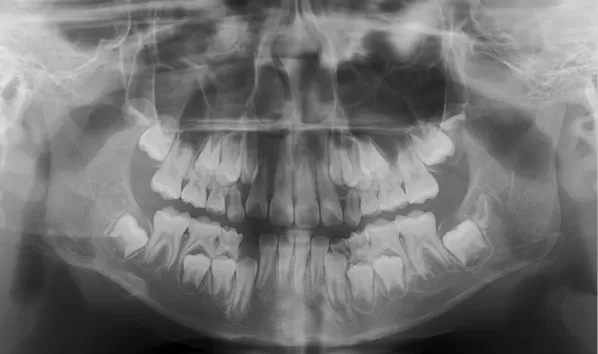

X-rays before treatment

[Panoramic Radiography/Lateral Cephalogram]